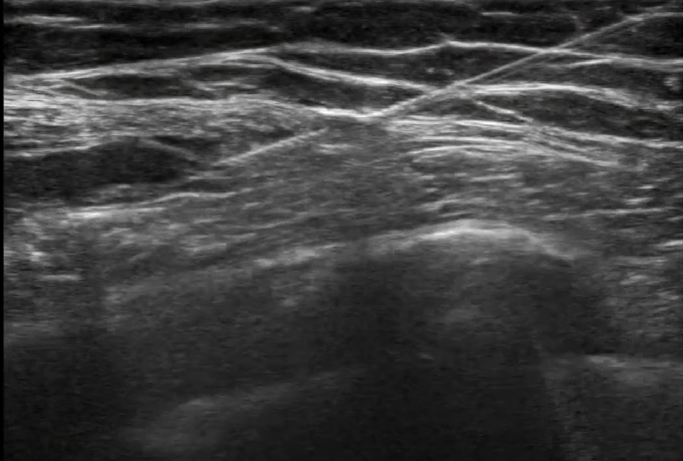

• Green = latissimus dorsi

Blue = serratus anterior

Yellow = intercostal muscle

White = rib

Red = pleura

• Either superficial or deep to serratus anterior muscle (in the clip, LA is being injected in the plane superficial to serratus)